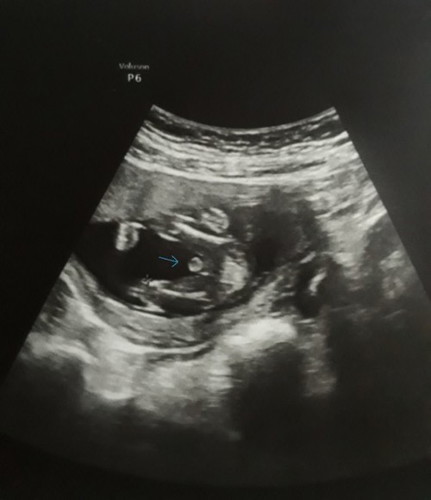

15week แบบนี้ผช.เเน่นอนเลยใช่มั้ยค่ะ

ชัดๆแบบนี้ผช.ใช่มั้ยค่ะ บอกที่บ้านว่าได้ผช.ไม่มีใครเชื่อเพราะเขาดูไม่เป่นกัน ที่บ้านว่าถ้าผช.แม่ต้องหน้าเป่นสิวต้องโทรม แต่เเม่ปกติดีไม่เเพ้ท้องเลยค่ะ

ผู้ชายชัดเจนเลยค่ะแม่ บ้านนี้ก็ไม่แพ้ท้องเลยค่ะ หน้าใส ไม่มีสิว ได้ลูกผู้ชายค่ะ